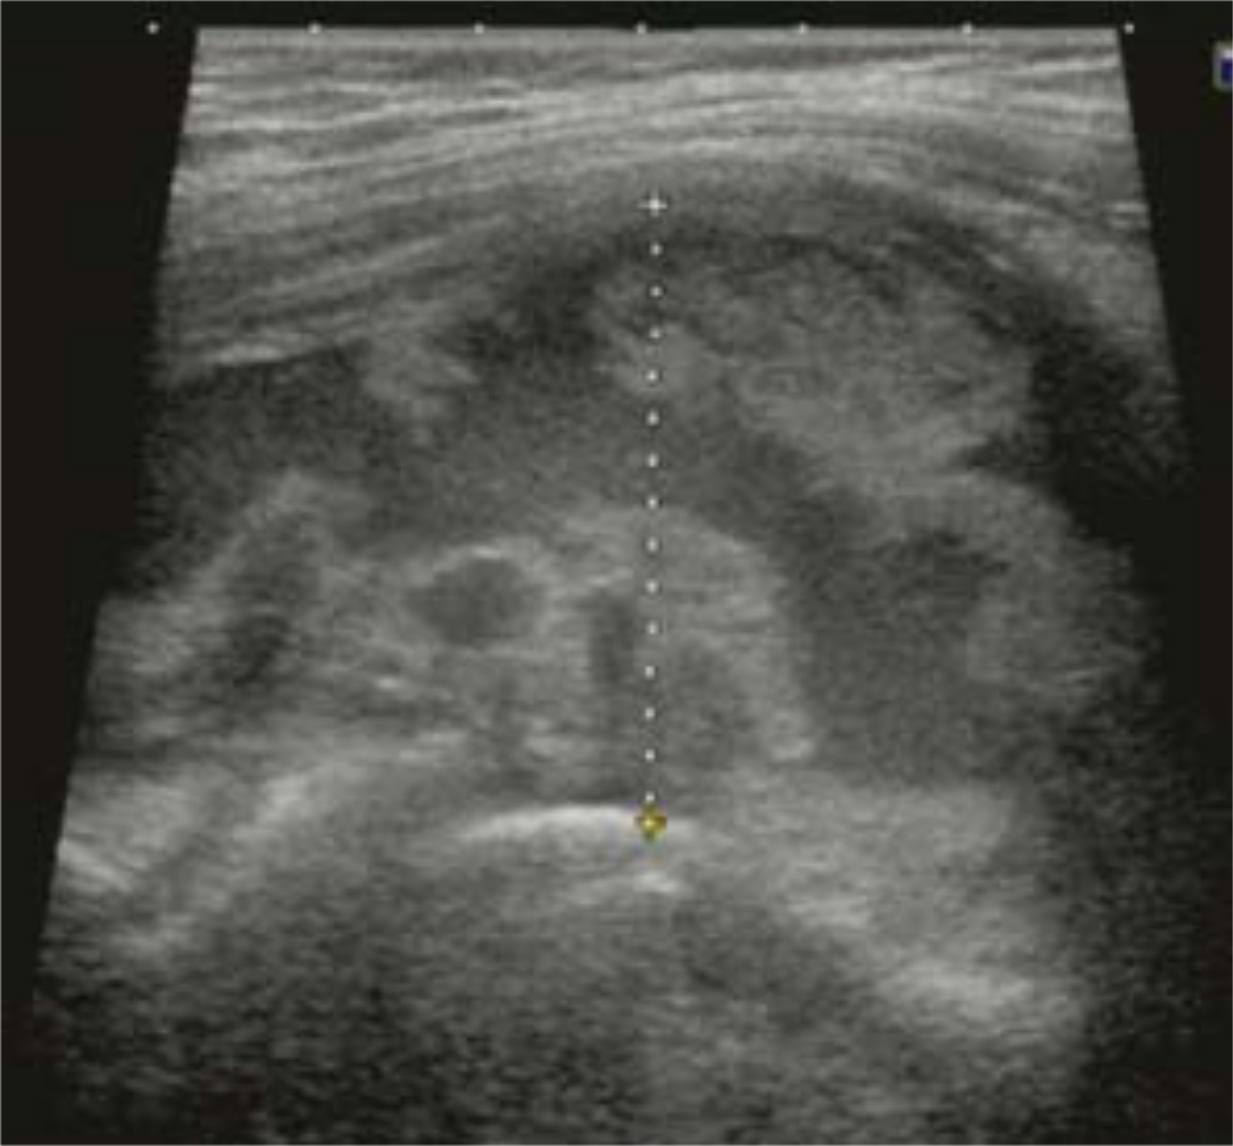

She was reviewed 2 years later and found to have no pain, a normal range of hip motion, and able to fully weight-bear without supporting aids, but she had a clicking and clunking sensation during index hip flexion moment 23 months postoperatively. At the same time, she noticed a soft tissue mass in her right inguinal region. Inflammatory serology was normal. The serum cobalt and chromium ion levels were 2.4 ng/ml and 0.05 ng/ml, respectively. Plain radiographs did not show any impending implant failure, but calcar osteolysis was visible (Figure 1). An ultrasound scan (APLIO XG SSA-790A PLT-805AT, Toshiba Medical Systems Corp., Tokyo, Japan) showed a mixed fluid and solid mass (Figure 2).

Figure 2 :Ultrasound scan, lateral to anterior, of the hip in Case 1, demonstrating a mixed fluid and solid mass.

Figure 10: Pathological specimen of Case 2 (hematoxylin and eosin, ×20). See text.

To identify these reactions, a specialized metal artifact reduction sequence (MARS) MRI has been recommended [26]. However, our institution was not equipped with this expensive system, and diagnostic ultrasonography was chosen as a screening tool instead [4,27,28]. As shown in Figure (2) and Figure (7), the latter tool was economical and cost-effective compared to MRI [29]. For arthrocentesis, it was easy to demonstrate the area of fluid collection. Finally, ceramic heads were used for revision surgery. This procedure was supported by several reports [19,26,30]. Goyal et al., reported good results of THA with adverse local tissue reactions by a ball (Co-Cr alloy) and liner exchange without stem (Co-Cr alloy) revision [31]. However, we chose ceramic heads for the newly implanted Profemur-R® stems and modular necks.